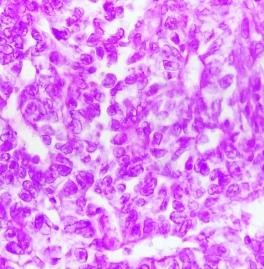

Dra. Grethel Villanueva Caballero

Anatomopatóloga

Servicios de Laboratorio en Anatomía Patológica

- Estudio histopatológico (biopsias y piezas quirúrgicas resección)

info@cepae.mx www.cepae.mx

- Estudio citopatológico (líquidos corporales)

- Análisis de litos

- Protocolos de investigación

- Estudios especiales (moleculares) (molecular